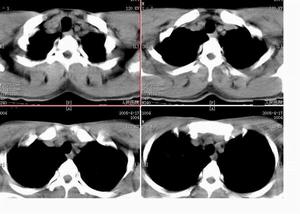

何杰金氏淋巴瘤CT圖HD的國際臨床分期(AnnArbor會議,1971)標準如下。